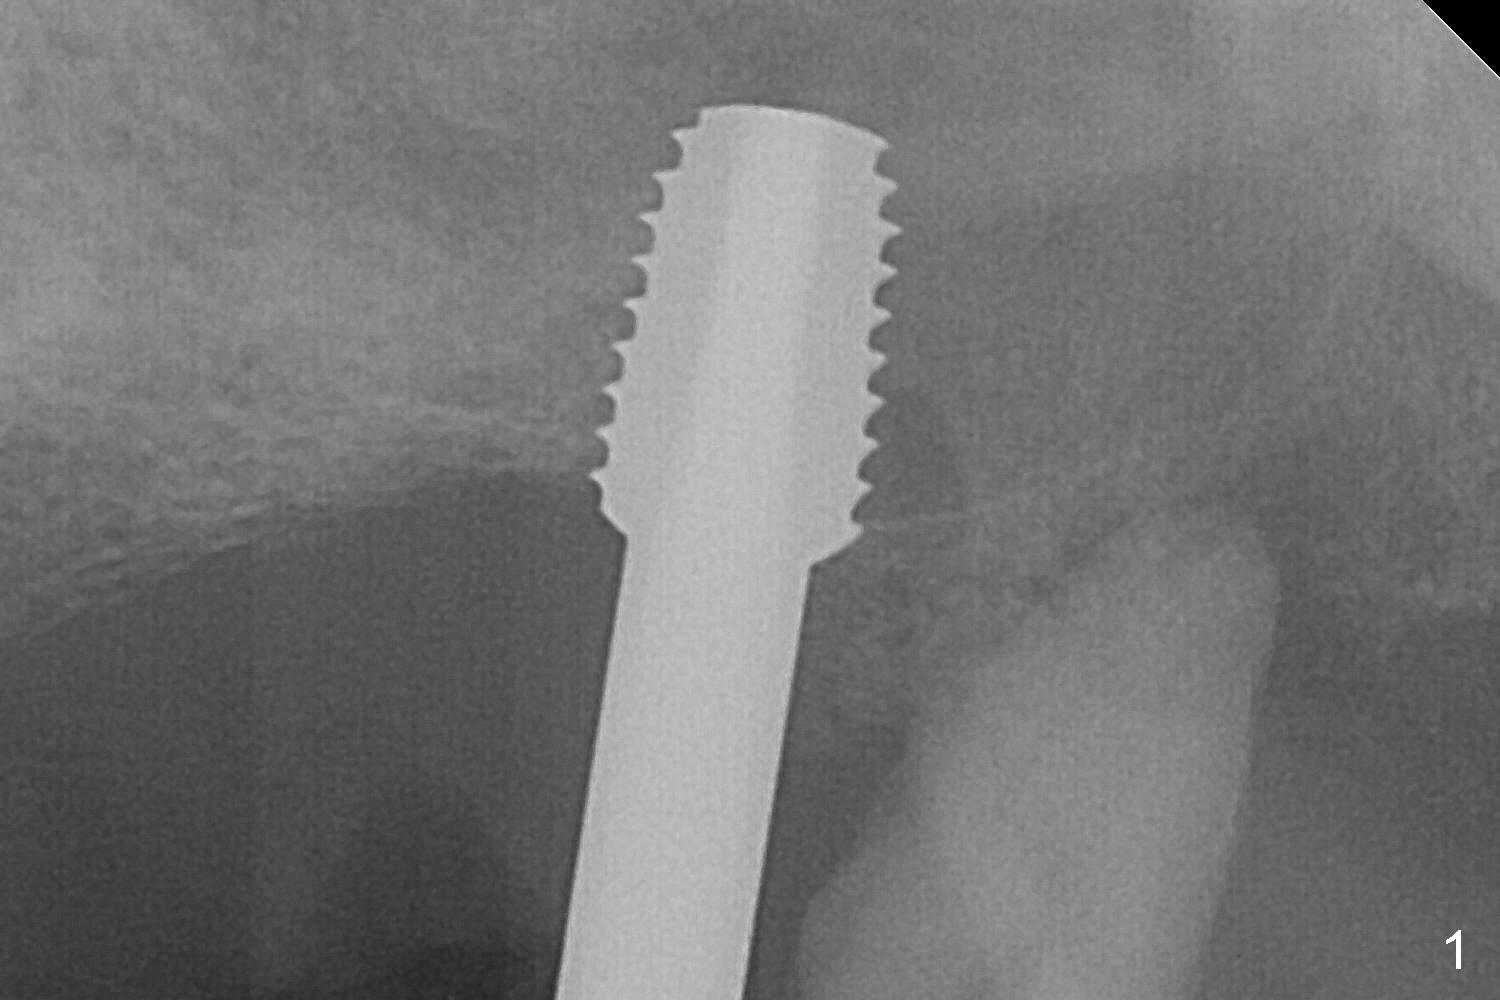

The posterior abutment of the 5-unit FPD, #15 is loose with the buccal roots extruded outside the sockets. The palatal socket is the appropriate site of immediate implant with the presence of the buccomesio-palatal walls, although short. The thinnest portion of the palatal socket is 1.6 mm (Fig.6 CBCT coronal section through the palatal root (P)). Magic Sinus Lifter cannot break through the sinus floor. UF drills are used to create osteotomy and sinus lift until 4.3 mm. A 5 mm tap drill is inserted without stability (Fig.1). A 5.5x9 mm IBS dummy implant achieves insertion torque of 10 Ncm, although it looks smaller (Fig.2) than the tap in Fig.1. After placement of PRF membrane and bone graft (allograft, autogenous bone and Osteogen, Fig.3 *), a 6x9 mm IBS implant is placed with insertion torque of 30 Ncm. It appears that the fins of the implant slice into the bone at high magnification for engagement. Following further placement of the implant, bone graft is packed into the distal portion of the socket (Fig.4 <). The thin fins extends into mesial and distal thicker bone (Fig.5 (CBCT sagittal view) *).